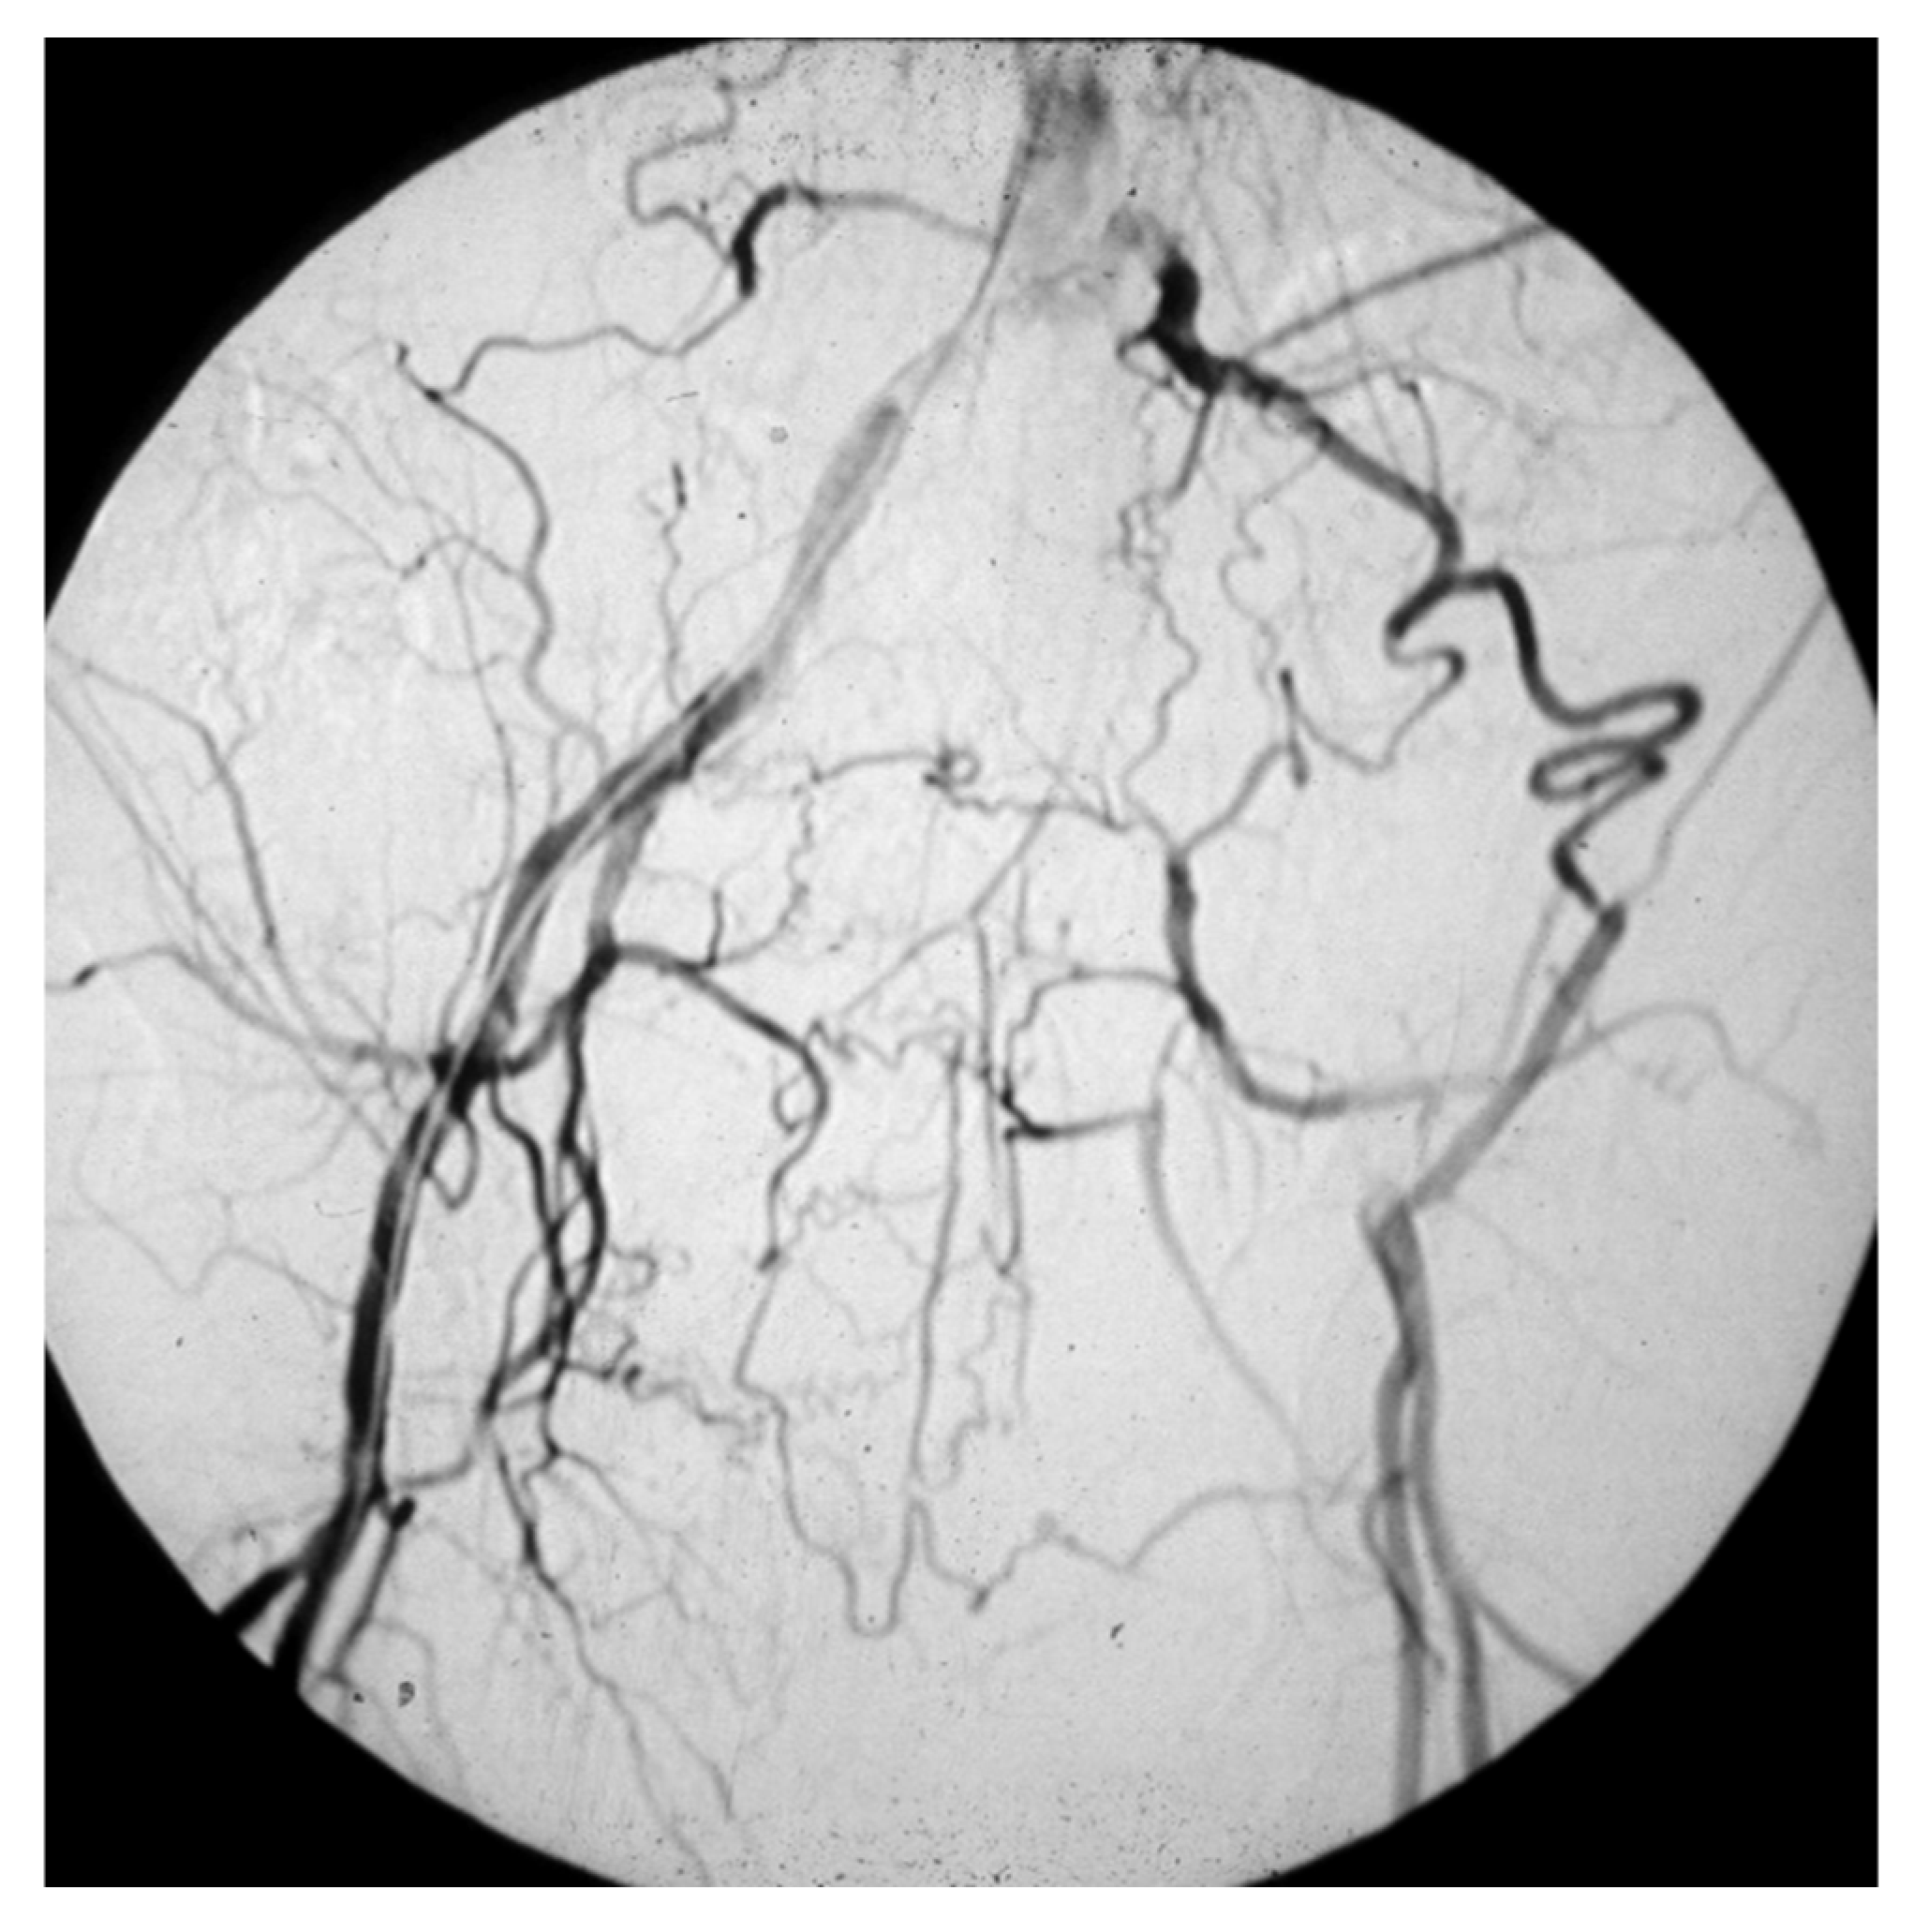

- those who have a masked LEAD, since they do not present IC: reasons range from the development of efficient arterial collateral circulation (Figure 6) to limited mobility, up to bedridden [45];

Figure 6. Arteriography showing obstruction of the left iliac axis, with an efficient collateral pathway revascularizing the common femoral artery. Depending on his/her age and lifestyle, this patient can eventually be asymptomatic or pauci-symptomatic for intermittent claudication. An accurate physical examination (detecting the absence of the left femoral pulse), and the subsequent left ankle-brachial index (founded to be reduced) can easily allow to classify this patient as vasculopathic.